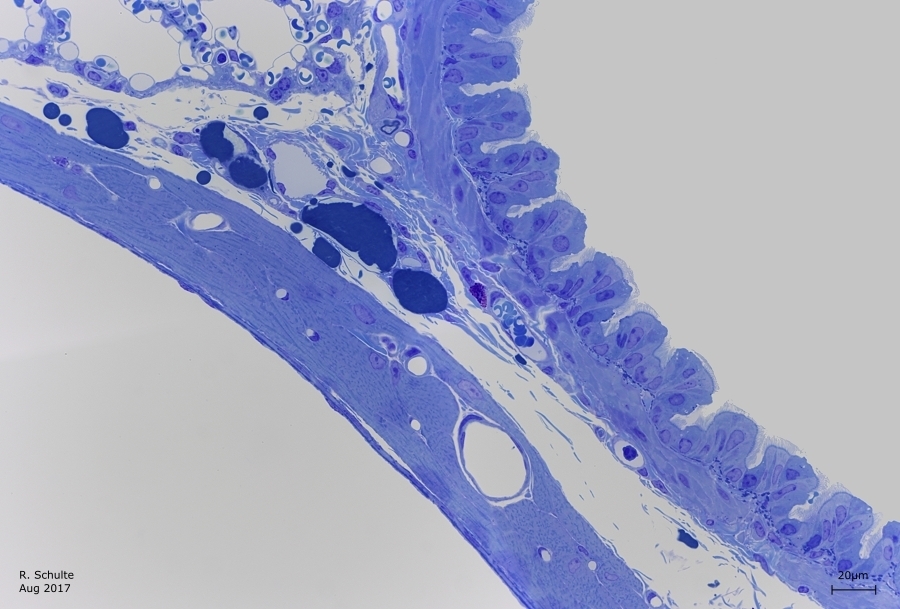

Das Gewebe wurde Perfusion Fixiert in ein Gemisch von Glutaraldehyde und Formalin. Um noch mehr Detail zu behalten wurde als zweit Fixativ Osmium Tetroxid genutzt. Wie folgende Bilder zeigen sind die Fettzellen, die z.B. bei eine Formalin oder Bouin Fixierung ,Leer' sind, hier nicht Leer sondern ist das Fett enthalten geblieben.

Die Schnittdicke liegt bei 0,8µm und die Farbung ist eine Basische Toluidin Farbung.

Die Massiv blaue Zellen sind Fettzellen (nach Osmium Fixierung wird das Fett nicht ausgelöst).

Gans in die Mitte ist noch eine Mastzelle zu sehen und geubte Augen können auch ein Nerv entdecken.

Orange Markieren die Raumen wo sich Blut befindet, alle andere Raumen sind Luftraumen.

* = Luftraum;

A = Erythrozyten (Rote Blutzellen);

B = Endothel Zelle eine Alveolarsepten;

C = Weiße Blutzelle;

D = Pneumozyte;

E = Alveolarmakrophage mit Zell Trümmer;

F = Blut-Luft Schranke;

G = Blutkapillaren (bei Perfusionsfixierung werden die meisten Blutzellen ausgespült).